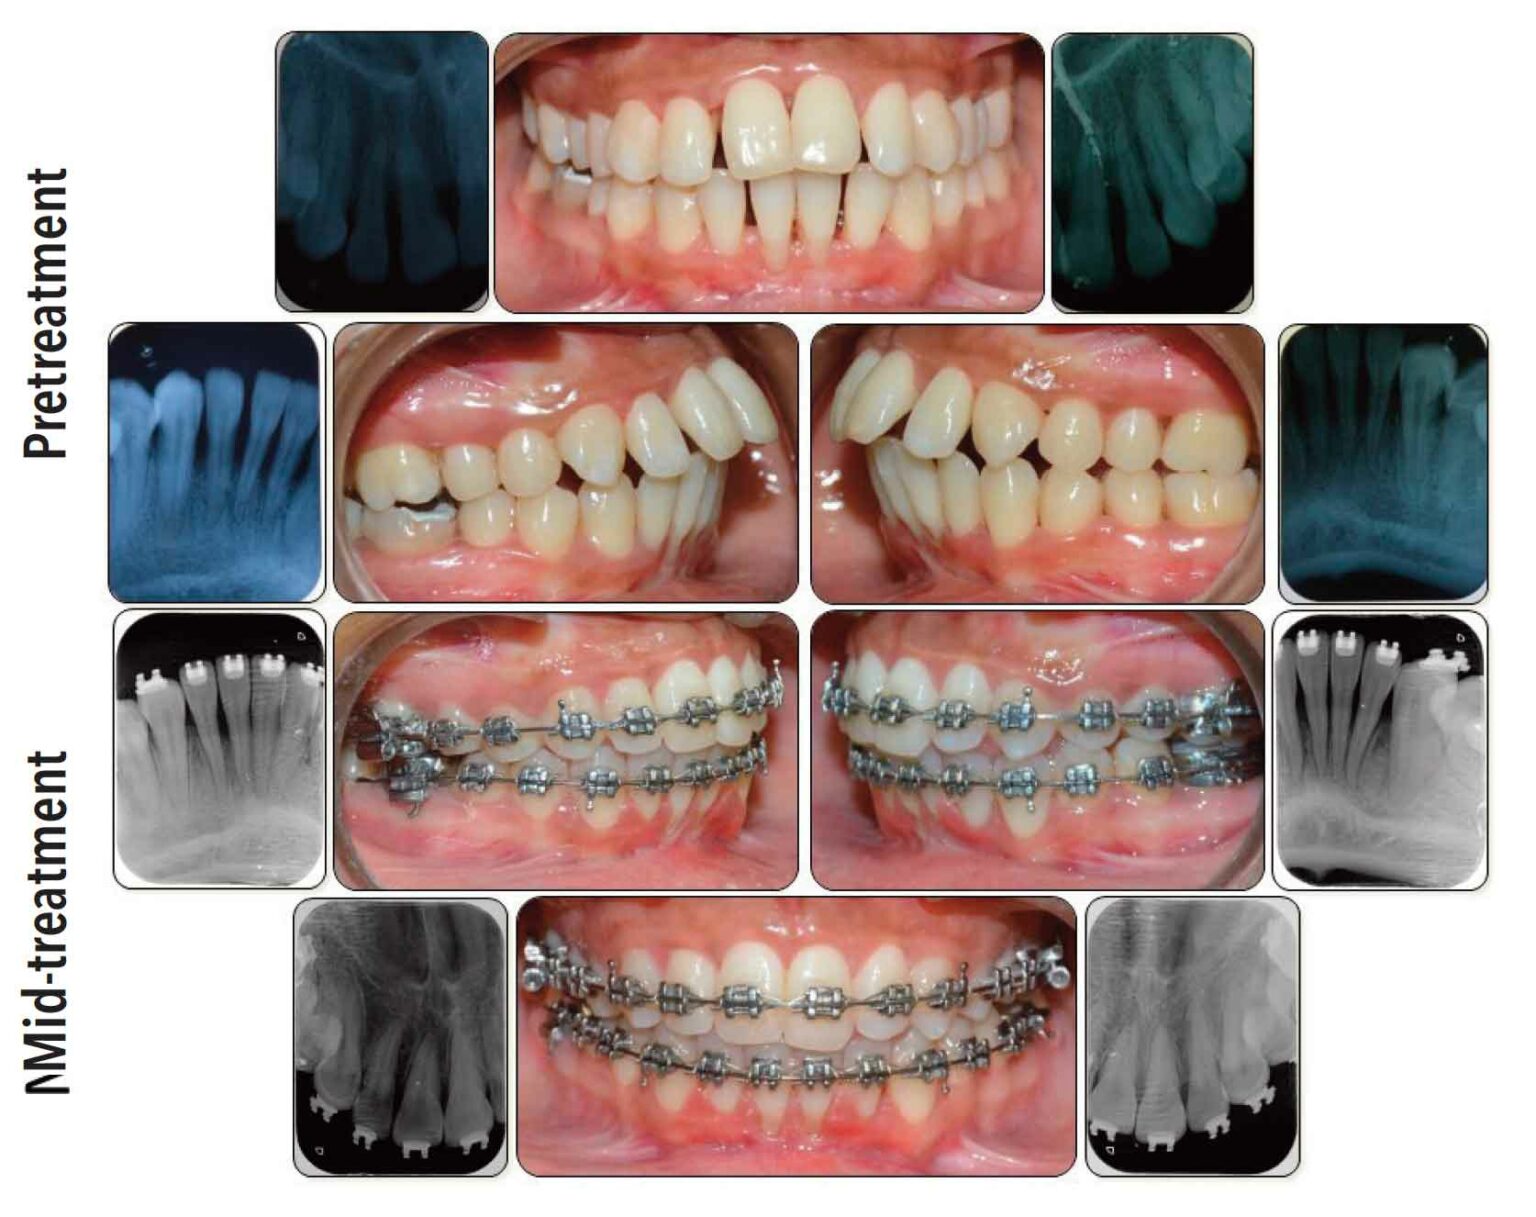

From periobasics.com

Orthodonticperiodontal interrelationship Examples Of Orthodontic Cases systems and orthodontic materials continue at some considerable pace within the profession, which provides considerable. Invisalign (1) the invisalign clincheck virtual simulation. having a clear understanding of the interaction of orthodontic therapy and temporomandibular joint function is. the following sample questions and answers were composed and vetted by a panel of experts in orthodontics and are intended.. Examples Of Orthodontic Cases.